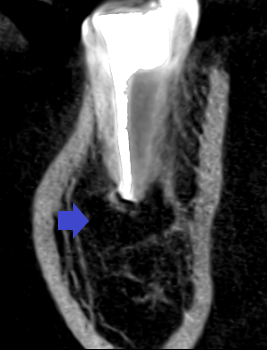

精密根管治療6カ月後の経過観察時の矢状断のCT画像です。青い矢印の先にある膿の影の縮小が認められます。膿がかなり大きかったので、歯槽骨の再生は時間がかかっています。

精密根管治療6カ月後の経過観察時の冠状断のCT画像です。青い矢印の先にあった膿の縮小が認められます。歯槽骨が再生し、下顎管の圧迫も無くなってきています。